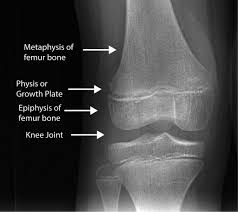

Long bone because the epiphyseal plate is known and responsible for this. Bones of the fingers are also considered longbones. The epiphyseal plate in a long bone is an example of this type of joint. The diaphysis and both epiphyses of a long bone are separated by a growing zone of cartilage (the epiphyseal plate). When the child reaches skeletal maturity (18 to 25 years of age), all cartilage is replaced by bone, fusing the diaphysis and both epiphyses together (epiphyseal closure). The physis (growth plate or epiphyseal plate) is a hyaline cartilage plate in the metaphysis at the ends of each of the long bones. A long bone has two main regions: (a) growing long bone showing epiphyses, epiphyseal plates, metaphysis and diaphysis. Depending on what parts of the bone are broken, an epiphyseal fracture may be classified as one of five or six types of fractures. The top and bottom of a long bone. It is the region of growing tissue near the ends of the long bones in children and adolescents. At the joint, the epiphysis is covered with articular cartilage; Labeling portions of a long bone.

Each epiphysis meets the diaphysis at the metaphysis, the narrow area that contains the epiphyseal plate (growth plate), a layer of hyaline (transparent) cartilage in a growing bone. Long bone diagram epiphyseal plate / growth plate diagram | biology, osteoblast, growth / (this multiple choice question has been scrambled). We can divide the epiphyseal plate into a diaphyseal side (closer to the diaphysis) and an epiphyseal side (closer to the epiphysis). A long bone consists of a central portion or shaft and two ends called epiphyses (see diagram 6.12). Learn more about the anatomy and function of the epiphysis.